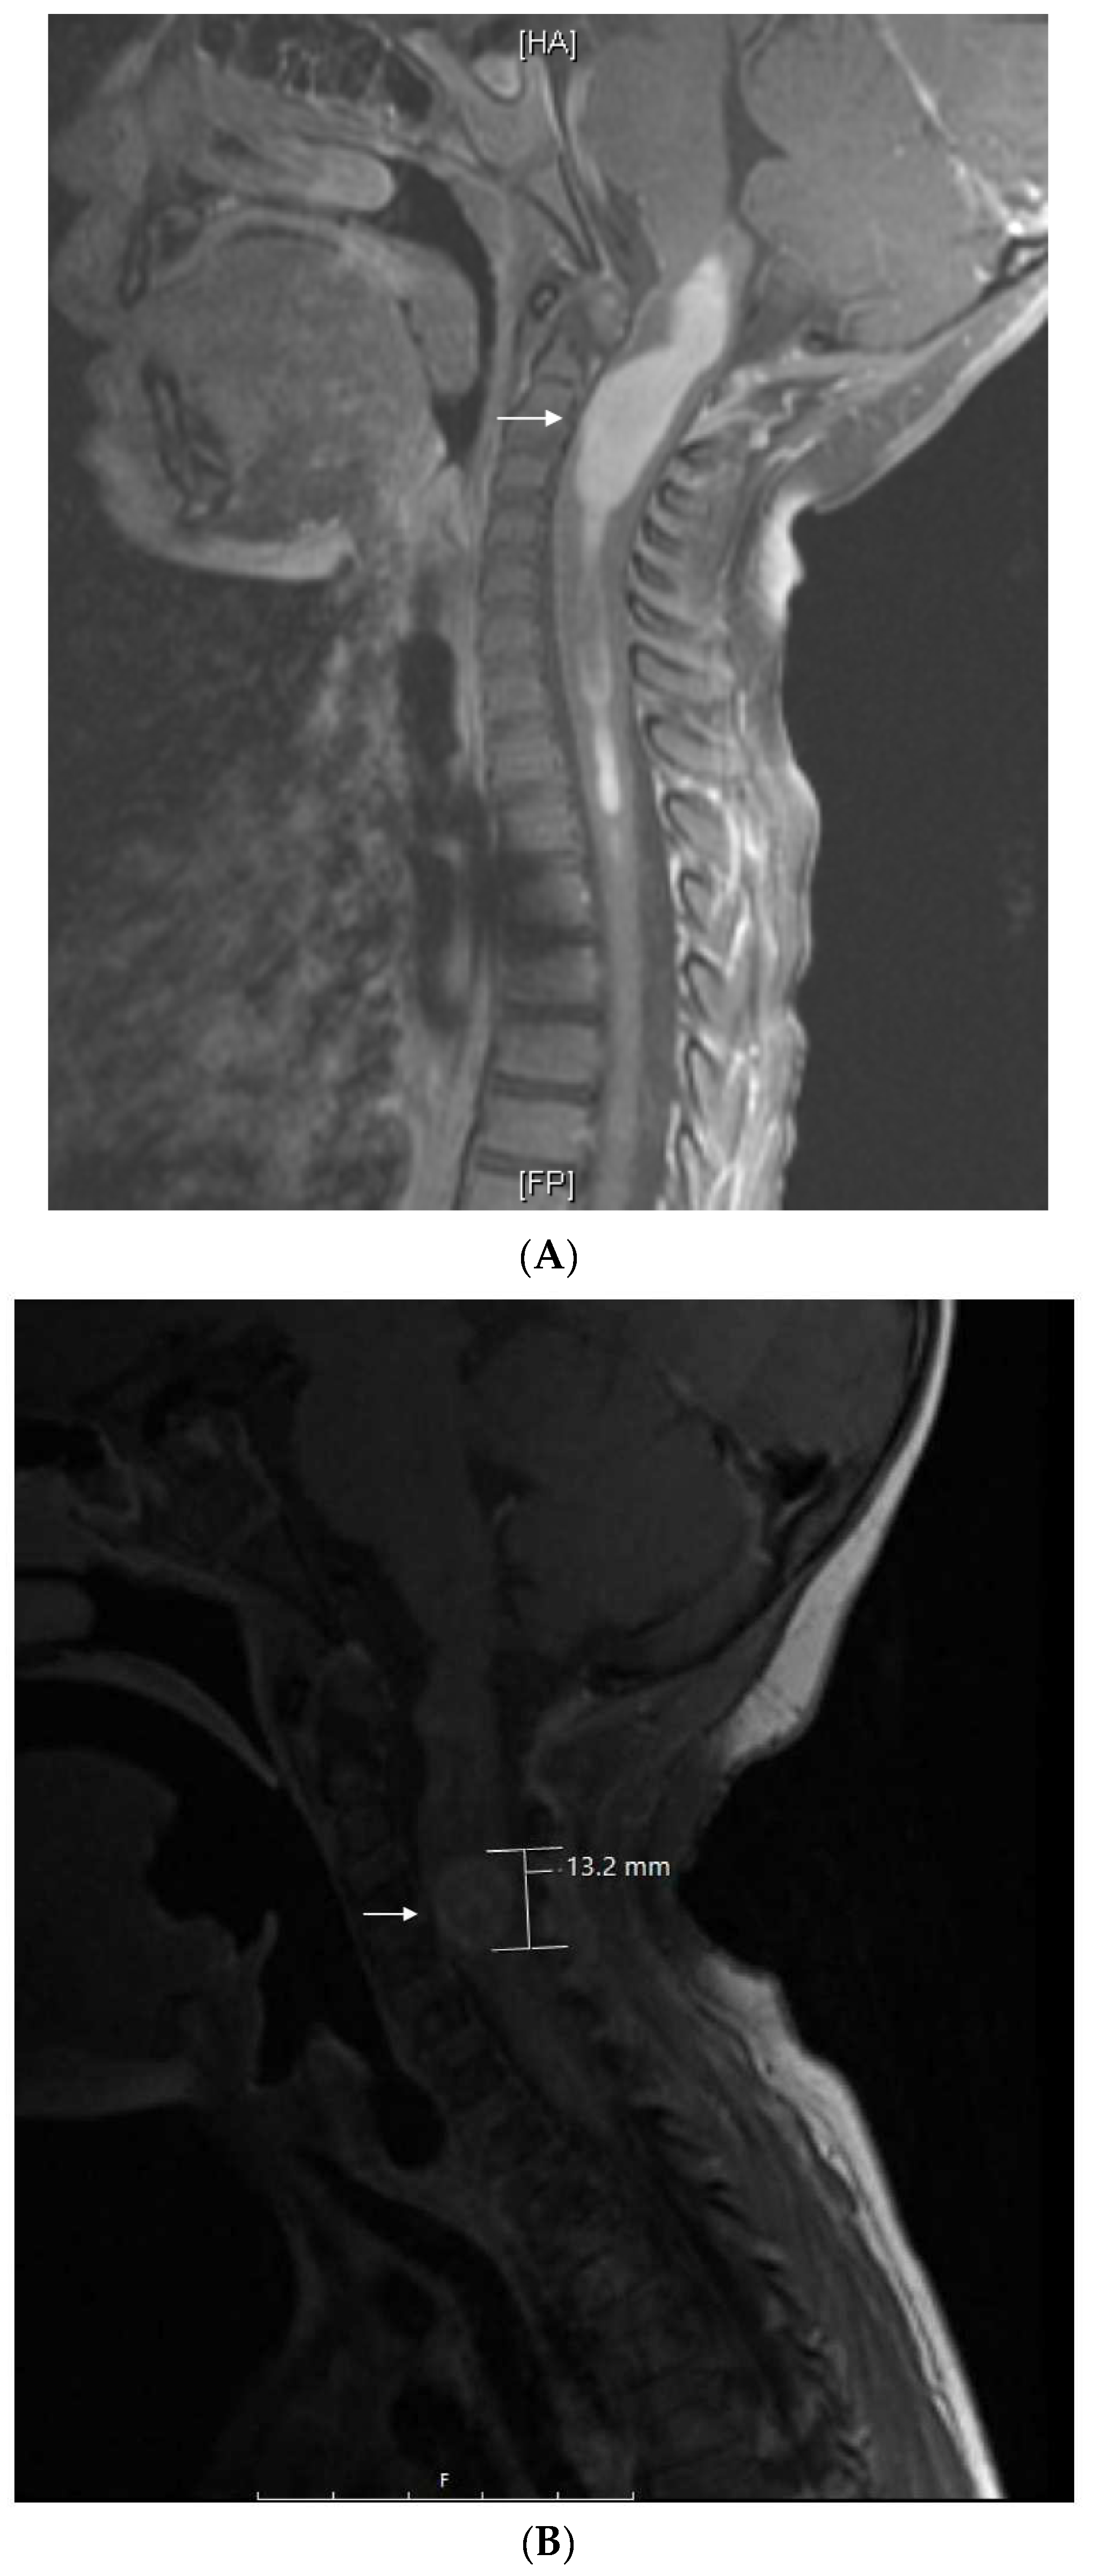

| 2 | Supratentorial Anaplastic Ependymoma. Local and distant relapse to spine. | VP16-CTX, Celecoxib, VA | 6 years | CR | CR 5.5 years at last encounter Alive 8 years at last encounter |

| 3 | Medulloblastoma Infratentorial Microscopic leptomeningeal relapse | VP16 alone (VA added later) | 10 months | CR | CR 5 years at last encounter Alive 7 years at last encounter |